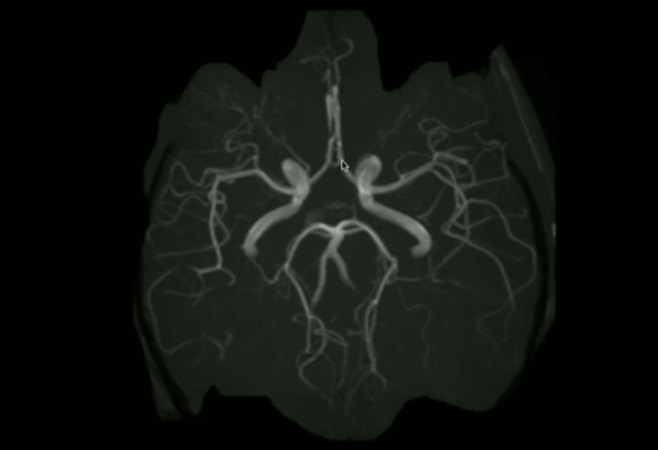

<p>What is the orientation + what are these vessels?</p>

What is the orientation + what are these vessels?

<p>Label these 3 vessels (inferior to superior)</p>

Label these 3 vessels (inferior to superior)

• Vertebral

• Basilar

• PCA